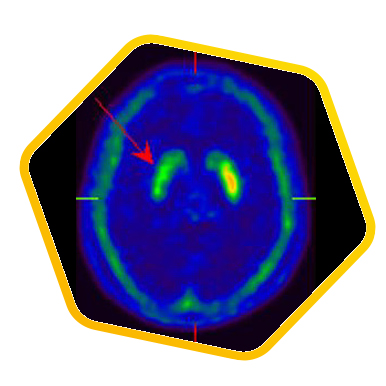

脑神经科

![]() [C-11] PIB |

![]() [C-11] Raclopride |

![]() [F-18] DOPA |